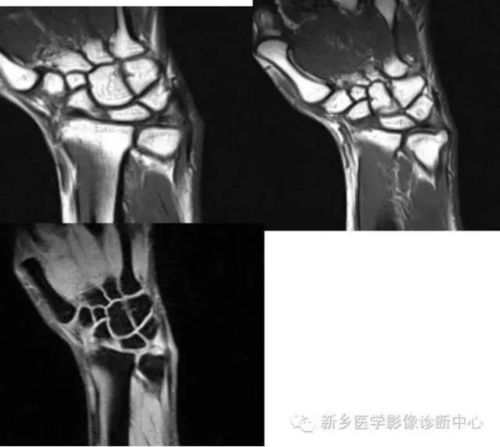

推荐| 三角纤维软骨复合体(tfcc)损伤

三角纤维软骨复合体损伤

三角纤维软骨盘损伤图

三角纤维软骨盘

三角纤维软骨盘撕裂